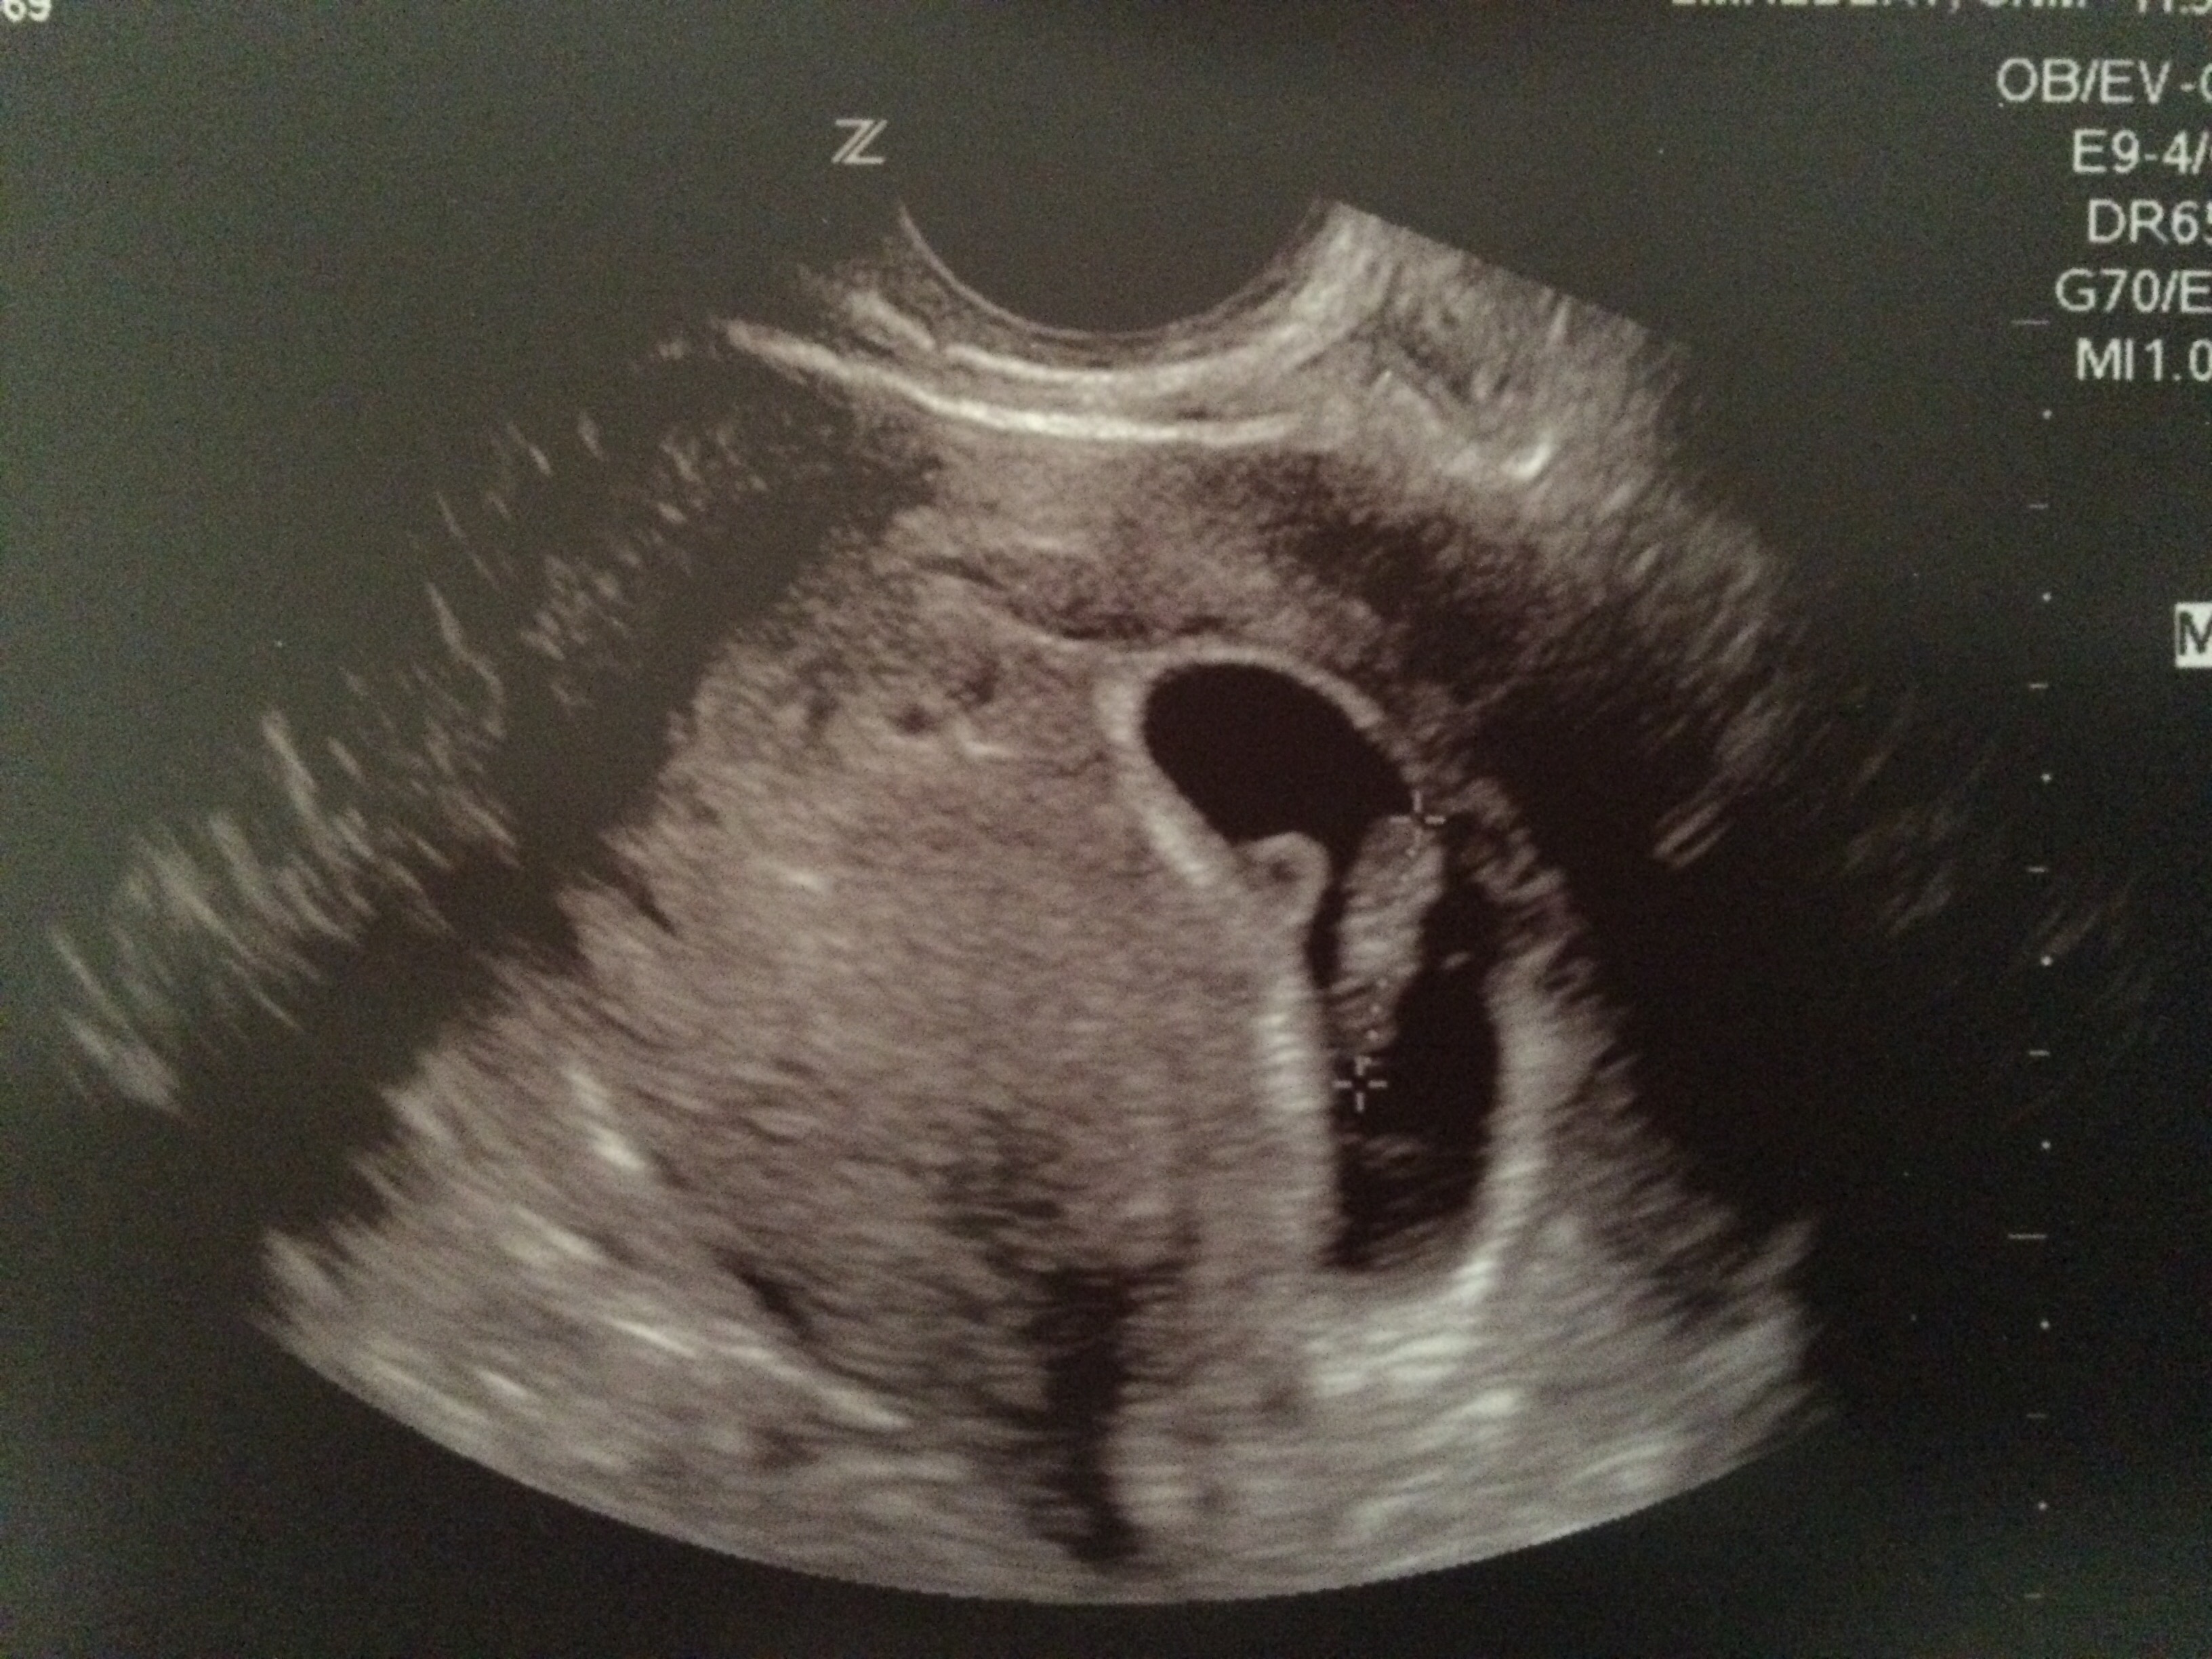

Here is our LO from our dating u/s yesterday (measuring 6w6d then, 7w today). It was so amazing & surreal to see its heart beating. I now fully understand "love at first sight." (So corny, I know lol)